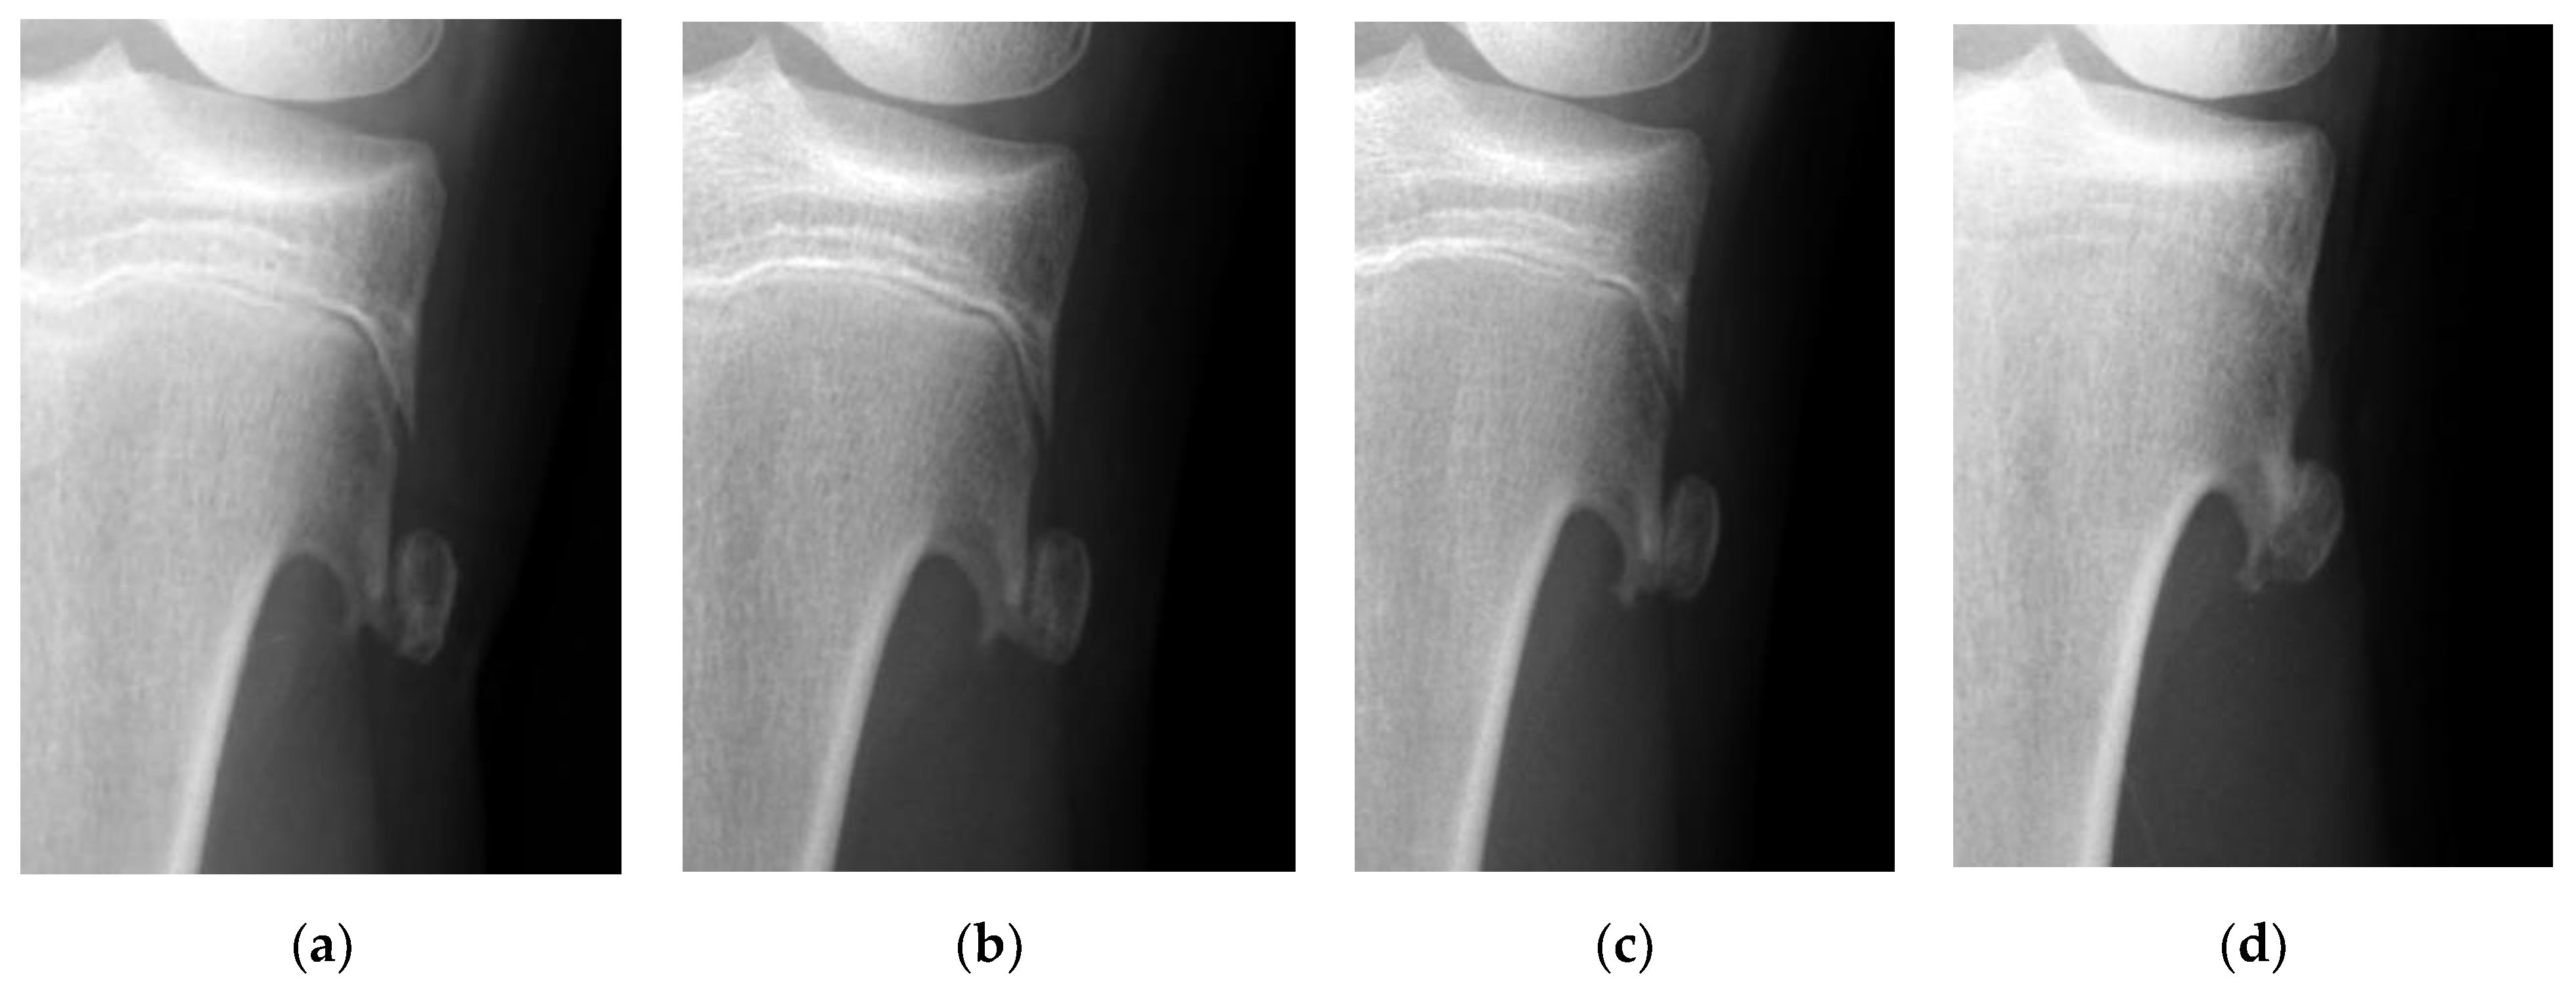

Figure 3. The radiographic views show sequential changes of the displacement of a fractured osteochondroma in the tibia. (a) Displacement of the fractured tibial osteochondroma is found in a 13-years-old girl who is a tennis player. (b) Union cannot be observed 4 weeks after the injury. (c) Partial union is achieved 1 year after the injury. (d) Complete union can be observed 5 years after the injury.

The mean time to return to the original sports activities was 2.3 weeks (range 1–4 weeks) in the surgery group. In contrast, the longest time required to return to original sports activities was 15 weeks in the one patient in the observation group. Surgery was not performed since pain subsided within 4 weeks after injury. However, this patient could not return to tennis due to the discomfort caused by a prolonged union; it took as long as 54 weeks to achieve partial union (Figure 3).